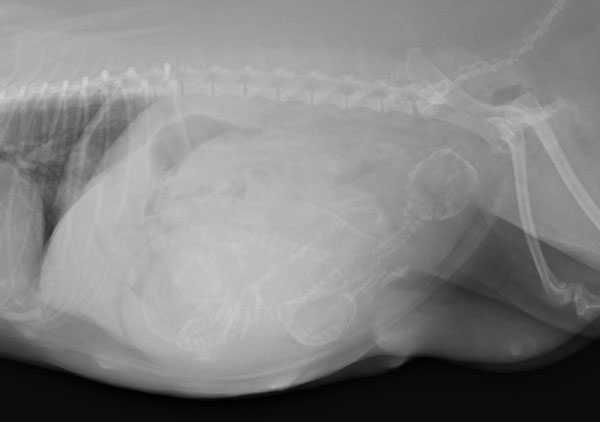

ワンちゃんが乳腺にできた複数のシコリを気にされて来院されました。bilateral mastectomyで対応しました。摘出後の病理組織検査の結果は、「R3-4間腫瘤:乳腺癌(複合型)」でそれ以外は「良性乳腺混合腫瘍」でした。無事元気に退院し、その後再発もなく経過は良好です。よかったね。